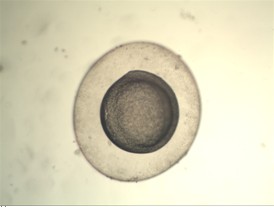

卵胞浆内单精子显微注射-胚胎移植是通过显微操作技术将单个精子注入卵母细胞浆内使精卵结合受精,并将受精卵体外培养形成早期胚胎植入母体子宫内的一种较为精细、尖端的辅助生殖技术。主要适用于少弱畸精症,甚至经精液常规检查无精子而只要在附睾或睾丸内能取到活精子的患者。

胚胎移植中一个最主要的前提条件是在体视显微镜下挑选合格的胚胎,这需要在显微镜下长时间对胚胎进行比较和挑选,这使得工作人员的眼睛容易产生疲劳,进而会影响正确的判断。为了解决这个问题,山东省省立医院在经过多方了解,并与明美北京办事处的工程师进行沟通后,决定在现有的leica体视显微镜上加配显微数码成像系统,组合成数码体视显微镜,不但能实现电脑实时显示代替人眼,并拍摄图片作为数据保存,而且可以录制视频,方便同时进行教学。

下面是实拍的一些图片: